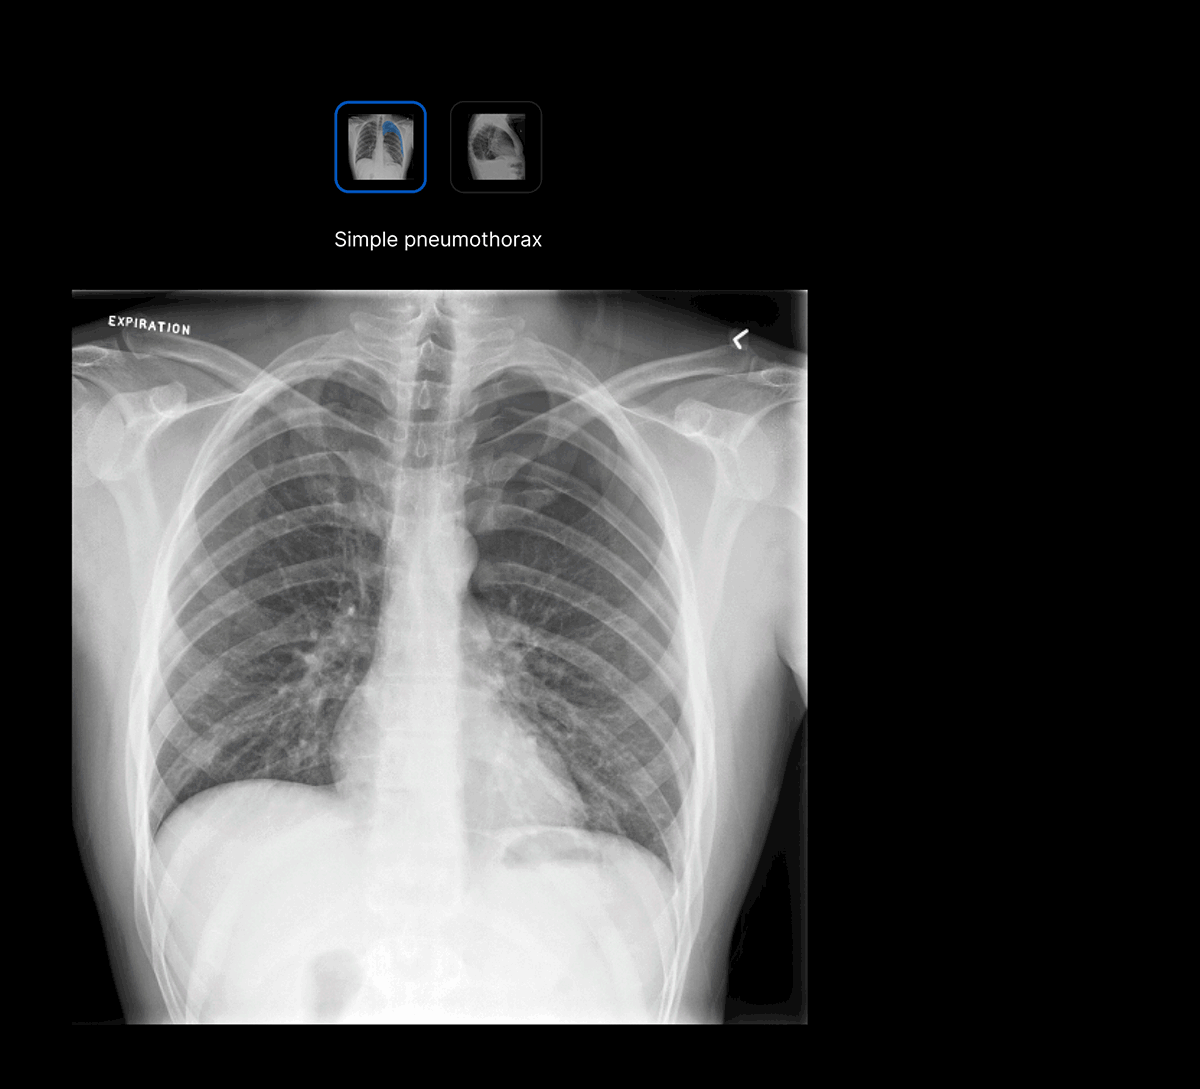

Facilitate accurate diagnoses of complex and subtle cases with AI-decision support identifying up to 124 findings on CXR and 130 findings on CTB.

The user-interface integrates seamlessly with PACS/ RIS, displaying a resizable, no-click overlay window with findings and localisation.

- Explainable AI features such as localisation and a confidence bar to improve AI interpretability and clinical decision making.